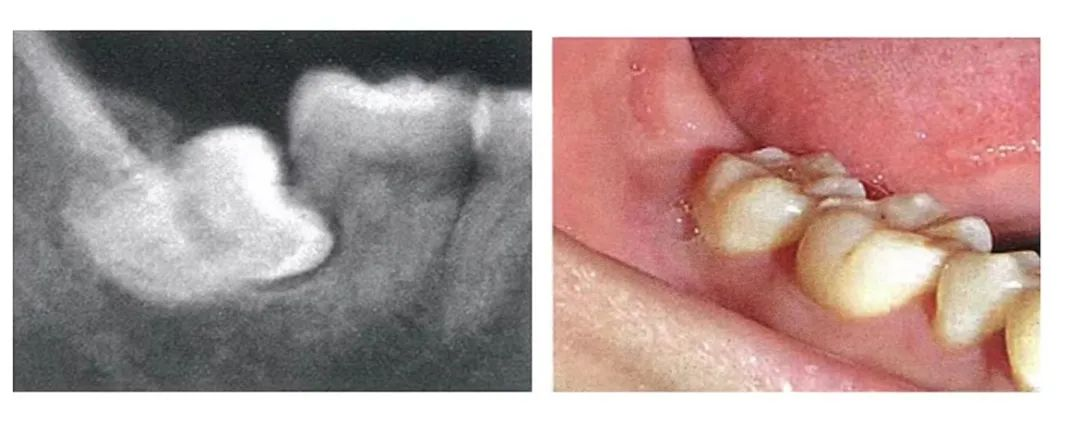

2.生长方向不佳的智齿

这种智齿无论是斜的还是躺着的,都走上了“细菌养殖业”的歪路,同样会让细菌腐蚀旁边的牙齿。

3.反复引起牙龈肿痛的智齿

牙齿的萌出需要过程,当部分牙龈覆盖在牙齿上面时,会形成盲袋,清洁不佳的情况下可因细菌积聚导致牙冠周围牙龈炎(冠周炎),从而出现肿痛。一般在牙齿完全萌出后,不适症状即可消失。如果肿痛反复出现在智齿的位置,那大多是由智齿萌出方向不正导致的。反复的智齿冠周炎轻则只是牙龈肿痛,重则可引起头颈部组织间隙细菌感染。